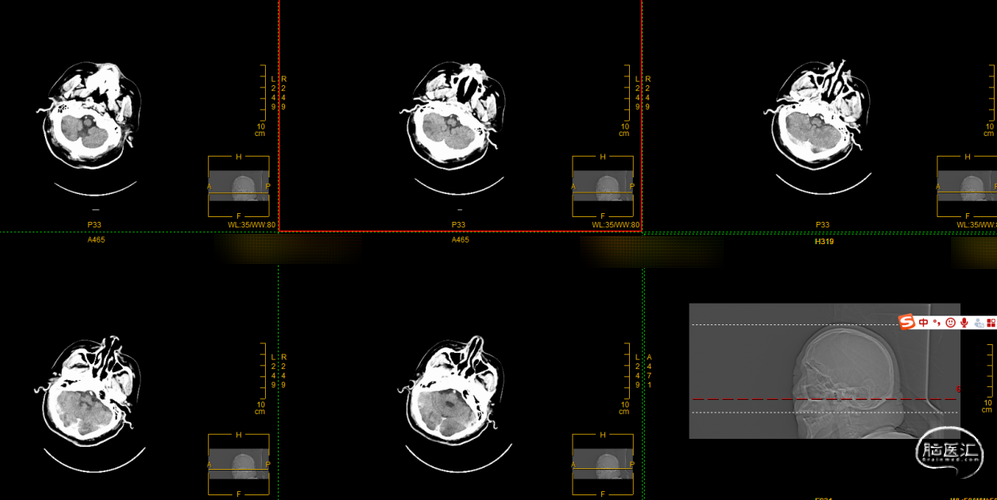

第二次拉栓后造影,血管再通,支架内再狭窄处理风险极高,且目前前向血流3级,对比造影时影像支架未有移位。

取栓后次日早晨复查头颅CT可见造影剂渗出,但患者已清醒,肢体自主活动可,言语不利、吐字不清,但他人尚易理解。